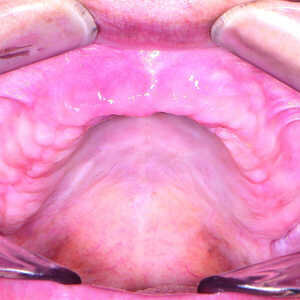

Fig-17-Crête-maxillaire-quatre-mois-après-l’intervention-300x300-

Fig-18-Crête-mandibulaire-quatre-mois-après-l’intervention-300x300-

Quatre mois plus tard (Figs. 17 et 18), les piliers de cicatrisation de l’arcade maxillaire ont été désenfouis par une technique chirurgicale, puis les tissus ont été soigneusement refermés. Après la cicatrisation, soit environ deux à trois semaines plus tard, des coiffes d’empreinte ont été mises en place sur les implants coniques Hahn et des empreintes ont été prises au moyen d’un porte-empreintes fermé et d’un matériau en polysiloxane de vinyle (Panasil, de Kettenbach). Un enregistrement de l’occlusion a également été réalisé (Futar, de Kettenbach). Les prothèses immédiates étant bien adaptées et satisfaisantes selon l’avis de la patiente, des répliques ont été envoyées au laboratoire aux fins de concevoir les restaurations définitives. Le laboratoire a utilisé les empreintes pour couler et scanner des modèles en plâtre-pierre, créer une image numérique des arcades de la patiente sur lesquelles les modèles des piliers personnalisés, et des restaurations à sceller ont été conçus. Les piliers personnalisés en titane Inclusive ont été fabriqués avec les composants du sourire en polyméthacrylate de méthyle (PMMA) correspondants.